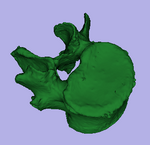

This dataset contains 3D modls obtained from in vitro CT of a human vertibral body segment (L4) before and after regional damage. Goal is to align the two models to study in detail the local changes that occurred and obtain estimates of structural integrity loss. Because the two orientations differ widely between acquisitions image-to-image registration has reduced robustness due to difficulty in initializing a good starting condition. Surface registration on the other hand is very robust toward strong difference in pose and he ce makes a good candidate for obtaining a fully automated first alignment.

4. Build Surface Models

1. go to the Model Maker module

2. Select preprocessed (see above) "intact_segfilled" as input volume

3. Create a new model hierarchy that will contain both models

4. Change model name to "intact_model1" or similar

5. set Labels field to 1.

6. uncheck the Skip Un-Named Labels box

7. increase Smooth parameter to 50

8. increase Decimate parameter to 0.35

9. uncheck boxes for Split Normals, Point Normals, Pad

10. click Apply

11. Repeat for second labelmap "defect_segfilled"